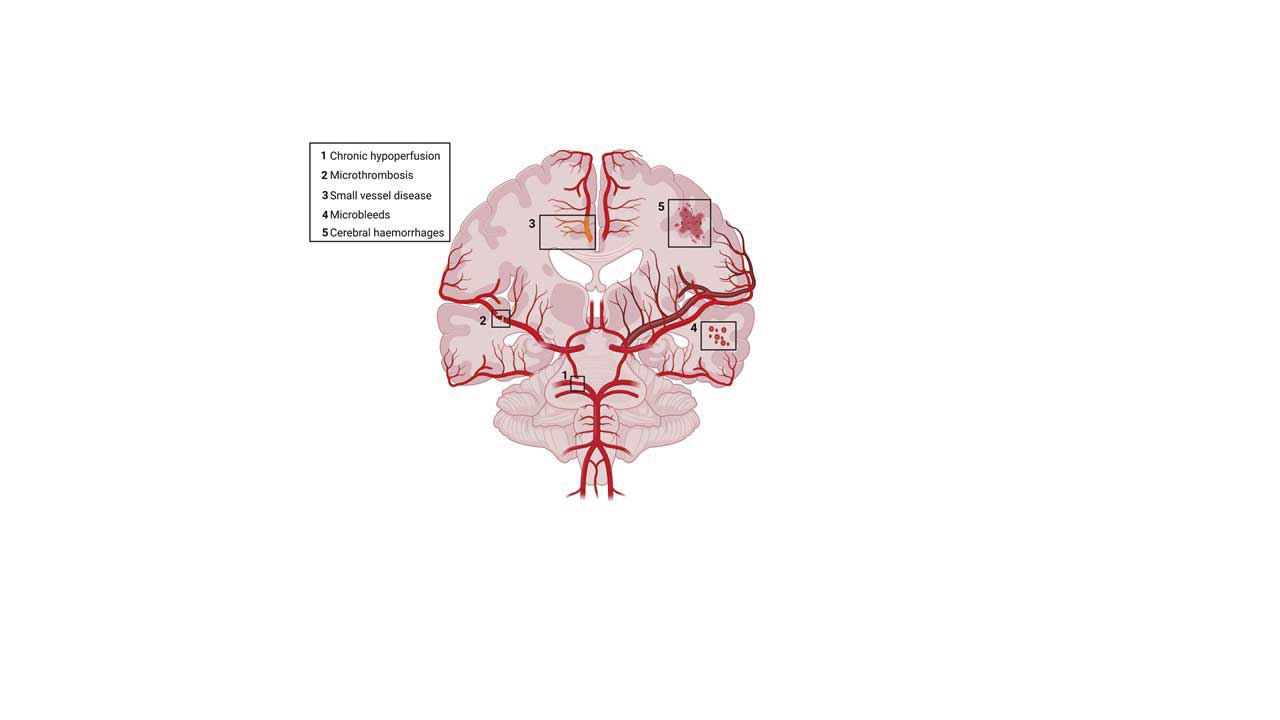

The Cardiovascular Risk Factors and Brain Health Program investigates how cardiovascular disease and its risk factors—such as hypertension, high cholesterol, obesity, and metabolic syndrome—affect brain function. Our aim is to use this knowledge to develop strategies for preventing cerebrovascular disease and cognitive impairment with age.

Drs. Moro and Cortes-Canteli edited a themed issue of the British Journal of Pharmacology entitled From Alzheimer’s Disease to Vascular Dementia: Different Roads Leading to Cognitive Decline (British Journal of Pharmacology, 2024a). This special issue reviewed several topics of core interest to Program researchers:

The clinical evidence on the effect of anticoagulants on the development of AD and other dementias (British Journal of Pharmacology, 2024b).

The complex interplay between microbiota and brain health, including the role of gut dysbiosis in cerebrovascular disease and its possible implications for post-stroke cognitive impairment and dementia (British Journal of Pharmacology, 2024c).

The contribution of the peripheral myeloid lineage to AD and vascular dementia, with a special focus on post-stroke cognitive impairment (British Journal of Pharmacology, 2024d).

Additionally, María Ángeles Moro’s team provided an overview of the circadian control of immune–vascular interactions both in steady-state and in pathological cardiovascular conditions, such as atherosclerosis and infarction (Circulation Research 2024b).